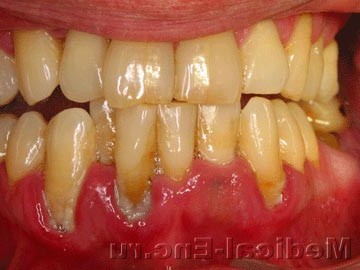

Зубна кіста - опухолеподобное освіта, що розвивається в щелепних кістках у зв'язку з запальними захворюваннями зубів або вадами розвитку. Зубна кіста являє собою порожнисте утворення, що складається з щільної оболонки, в якій міститься серозна рідина, насичена холестерином. Зубну кісту ділять на радикулярні (околокорневые) і фолікулярні (околокоронковые). Радикулярний зубна кіста розвивається з гранульоми (див. Гранульома зубна) під впливом хронічного запального процесу. Фолікулярна зубна кіста утворюється при ваді розвитку зубного фолікула (зубообразовательного епітелію), можливо, в результаті хронічного запального процесу у верхівок коренів молочних зубів; клінічно для неї характерна відсутність відповідного зуба.

Зубна кіста, як правило, розвивається повільно, безболісно. Досягнувши значних розмірів (3-4 см в діаметрі і більше), кіста проявляється припухлістю щелепи і асиметрією особи; відповідно руйнується кісткова тканина, яка, истончаясь, стає податливою при пальпації - виникає так званий симптом пергаментного хрусту.